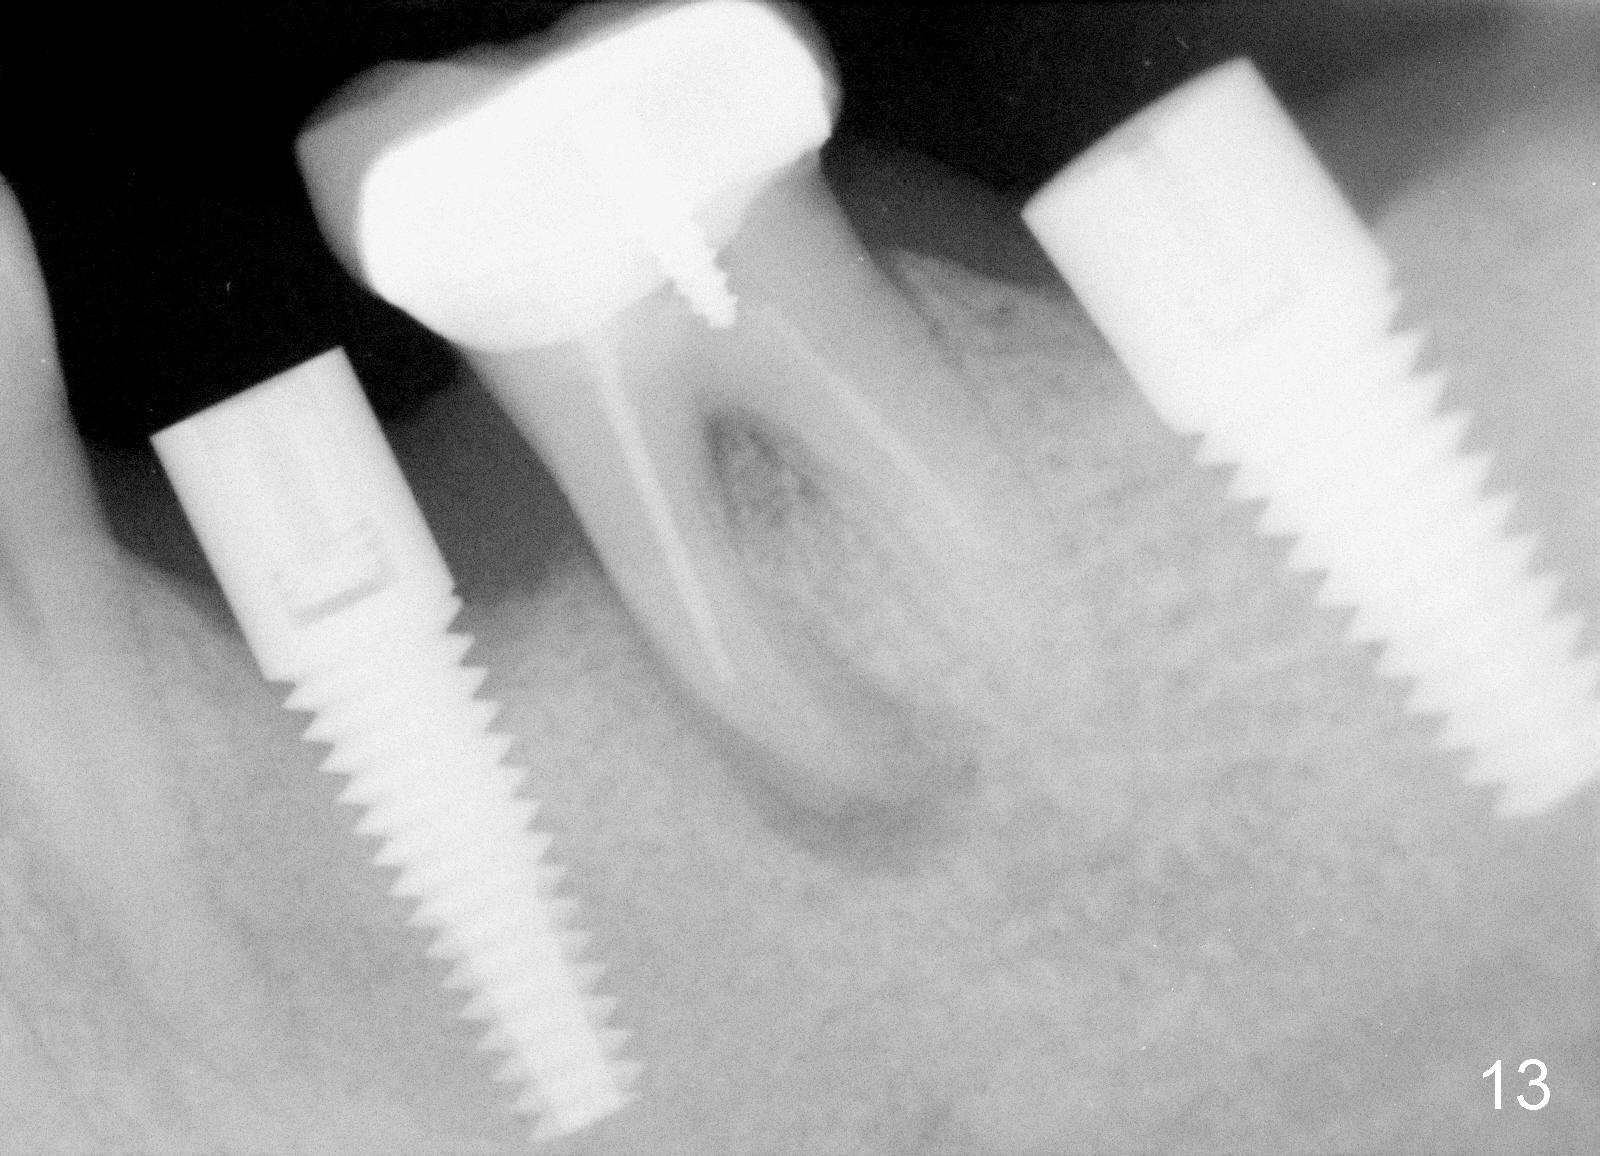

A 44-year-old lady has poor dentition. The tooth #20 has a residual root (Fig.1 R). Immediately after extraction, osteotomy is formed by drills (Fig.2: 3.5x17 mm); a 4.5x17 mm implant is placed (Fig.3 (arrowheads: boundary of the socket)). The patient returns 9 months later with increased radiolucency around the implant (Fig.4) and buccal swelling (Fig.5, asymptomatic). Raising the buccal flap confirms bone loss around the implant (Fig.6). Following debridement, allograft is placed. The source of the infection is unknown.